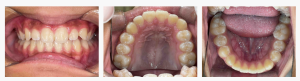

▼ Before(治療前)

◆ 診断名・初診時の状態

診断名:叢生(そうせい)・上顎前突

初診時の診察では、

・上の前歯が前に出ている(上顎前突)

・前歯が並ぶスペース不足によるガタガタ(叢生)

・口呼吸傾向があり、舌が低い位置にある

・口周りの筋肉バランスが弱く、歯列に影響が出やすい

などの所見があり、歯並び+機能面の問題 が組み合わさった状態でした。